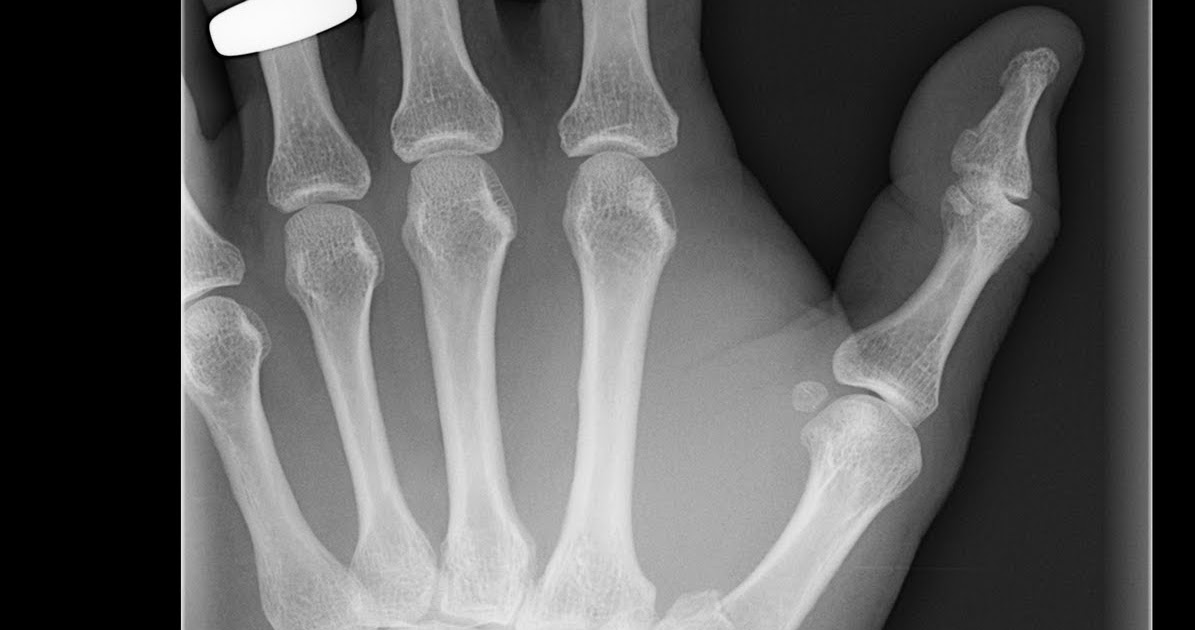

Bennett Fracture X Ray View . On these ct scans a bennett. radiographs of the carpometacarpal (cmc) joint are obtained by placing the palmar surface of the hand flat on the imaging plate for a true lateral.

Boxer fracture. Radiograph shows a fracture of the fifth metacarpal Bennett Fracture X Ray View radiographs of the carpometacarpal (cmc) joint are obtained by placing the palmar surface of the hand flat on the imaging plate for a true lateral. On these ct scans a bennett. Bennett Fracture X Ray View.